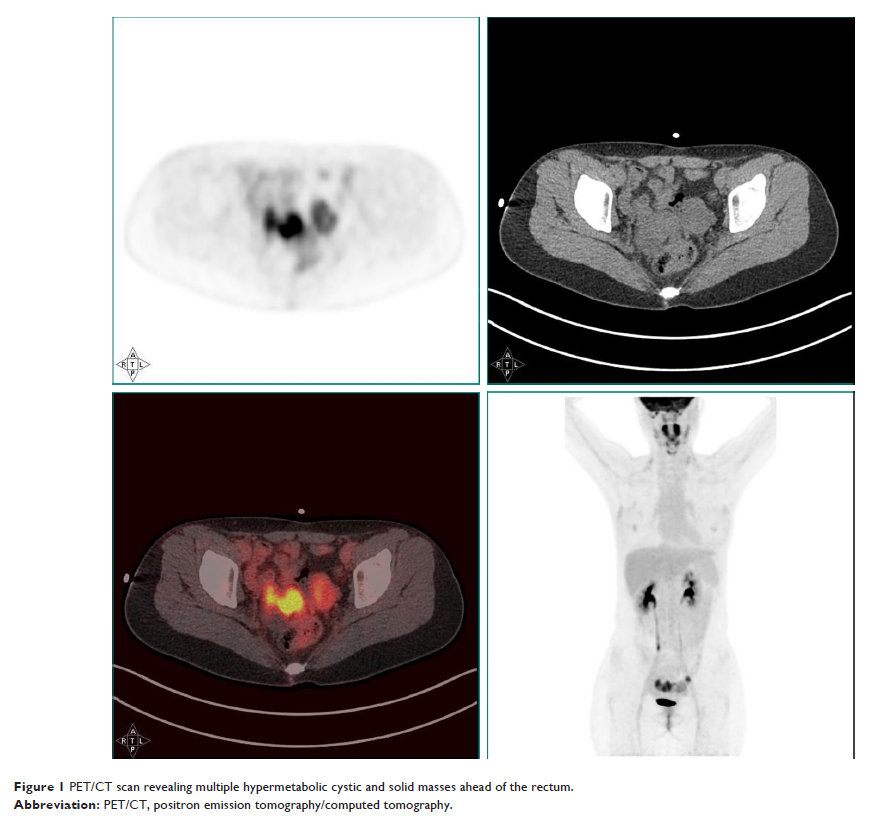

Case Report

- 作者:Zhen Yuan, Mei Yu, Yu Chen

- 期刊:OncoTargets and Therapy